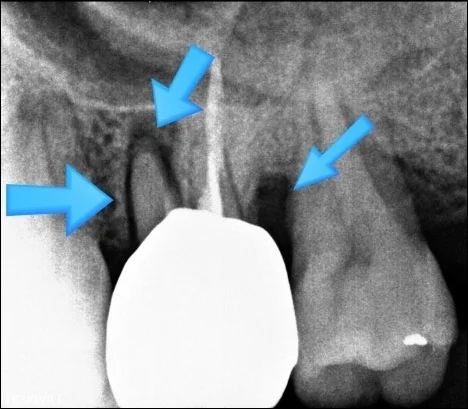

오산 치아진단 엑스레이 얼마나 꼼꼼히 하느냐가 중요합니다. 안녕하세요 서울버팀치과 엄용국원장입니다. “치과에 방문해 치료를 받았습니다.” 하지만 치과에서 치료를 받았다는 사실만으로 항상 적절한 치료가 이루어졌다고 단정하기는 어렵습니다. 정확한 진단을 위해서는 엑스레이 촬영...